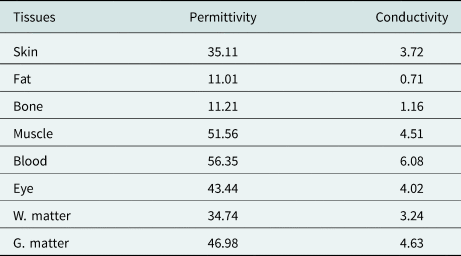

The head model consists of eight tissues: skin, fat, bone, eye, blood vessel, muscle, white matter, and gray matter. The mass density [Reference Kaburcuk and Elsherbeni20], relative permittivity, and conductivity of the head tissues calculated from Debye coefficients in [Reference Kaburcuk and Elsherbeni20] and [Reference Eleiwa and Elsherbeni38] for 2.4 and 5.8 GHz are tabulated in Tables 1 and 2. Figure 3 shows the human-head model's x–y, x–z, and y–z cross sections.

Table 1. Mass density, relative permittivity, and conductivity of the head tissues for 2.4 GHz

Table 2. Relative permittivity and conductivity of the head tissues for 5.8 GHz